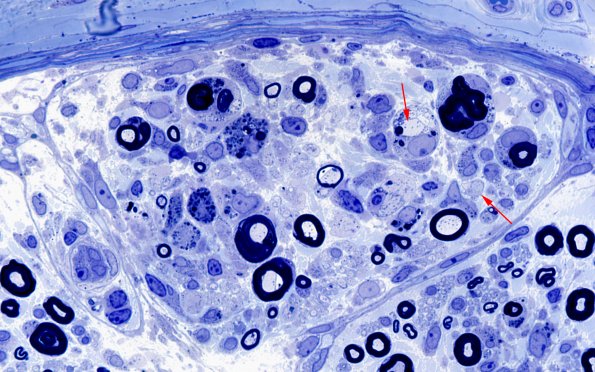

A closeup of one of the demyelinated foci showing demyelination (arrows). (Plastic section)